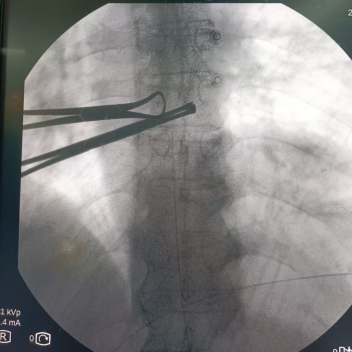

腹腔神经丛毁损术(三)

腹腔神经丛毁损术(CPN)是一种在影像学设备(如CT、X线或B超)精确引导下进行的微创介入治疗技术。其核心原理是通过穿刺针输送化学药物(如无水乙醇)或应用射频热凝技术,对支配腹腔上部脏器的感觉神经纤维进行毁损性阻滞,从而中断疼痛信号向大脑的传递。研究显示,该技术对胰腺癌、胃癌、肝癌、胆囊癌等所致腹部疼痛的缓解效果显著,有效率可达80%–94%,术后患者可显著减少甚至停用口服镇痛药物。